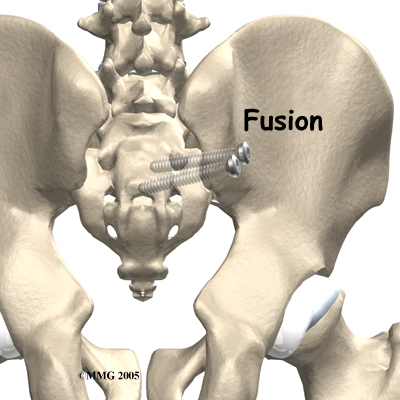

Surgery

Surgery may be considered if other treatments don't work. Surgery consists of fusing the painful SI joint. A fusion is an operation where the articular cartilage is removed from both ends of the bones forming the joint. The two bones are held together with plates and screws until the two bones grow together, or fuse, into one bone. This fusion stops any motion between the two bones and theoretically eliminates the pain from the joint.

This is a big operation and unfortunately is not always successful at relieving the pain. The operation is not commonly performed and is reserved only for use when the pain is debilitating and all other attempts at conservative treatment have failed.